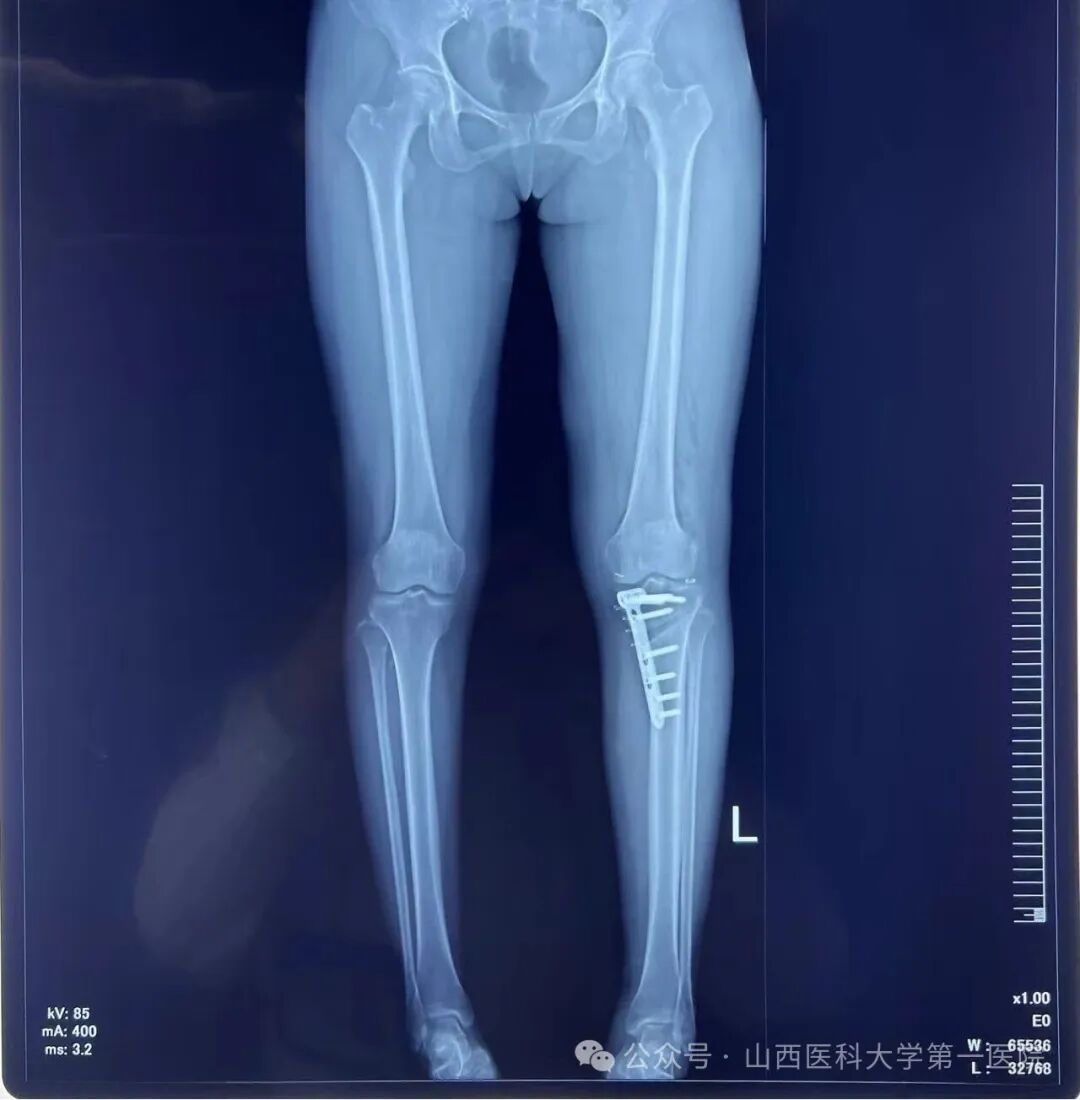

放置钢板后行X线确认位置满意

术后左下肢力线明显矫正